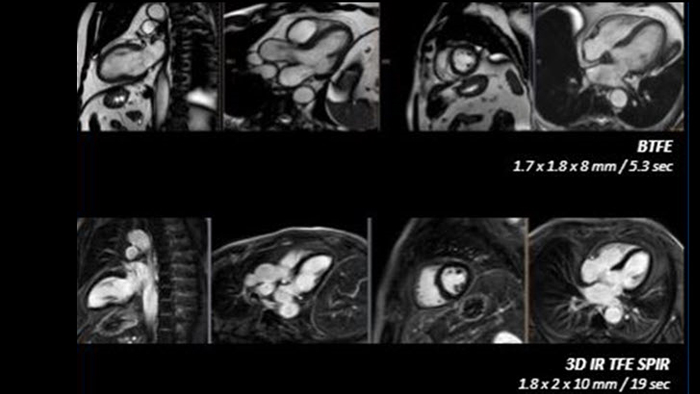

• Cardiac MR: lower scan times for high patient satisfaction while diagnosing early and confidently​.

High quality diagnostic imaging

Ingenia Ambition 1.5T

Realize the potential of MR throughout the pathway with ultrafast exams, optimized workflow, high-quality diagnostic imaging and enhanced patient comfort.